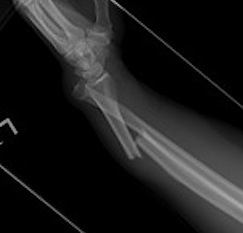

Shortening of radius with disruption of DRUJ on lateral

Concern for disruption of DRUJ on lateral

1. Anatomical ORIF of distal radius with dynamic compression plate

- anatomical reduction

- restoration of radial bow

- compression for healing

Radius ORIF with dynamic compression plates